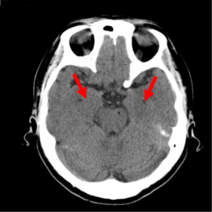

1985年 福島県⽴医科⼤学卒。様々な画像鑑定実績を有し、2011年よりメディカルリサーチ株式会社顧問医として交通事故をはじめとする様々なケースの画像鑑定を行い、交通事故態様、受傷態様から正しい症例把握や症例によって見られる複雑事案についても積極的に取組を展開している。